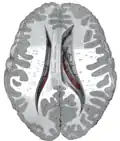

Transverse cut of brain (horizontal section), basal ganglia is blue | |

Along with the putamen, the caudate forms the dorsal striatum, which is considered a single functional structure; anatomically, it is separated by a large white-matter tract, the internal capsule, so it is sometimes also described as two structures—the medial dorsal striatum (the caudate) and the lateral dorsal striatum (the putamen). In this vein, the two are functionally distinct not because of structural differences, but merely because of the topographical distribution of function.